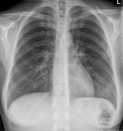

de

Ribben

un

Ruum

,

von

ümgeven

warrt

düütsch:

Brustkorb

Brustkasten

nedderlandsch:

borstkas

borstkast

ribbenkast

engelsch:

rib

cage